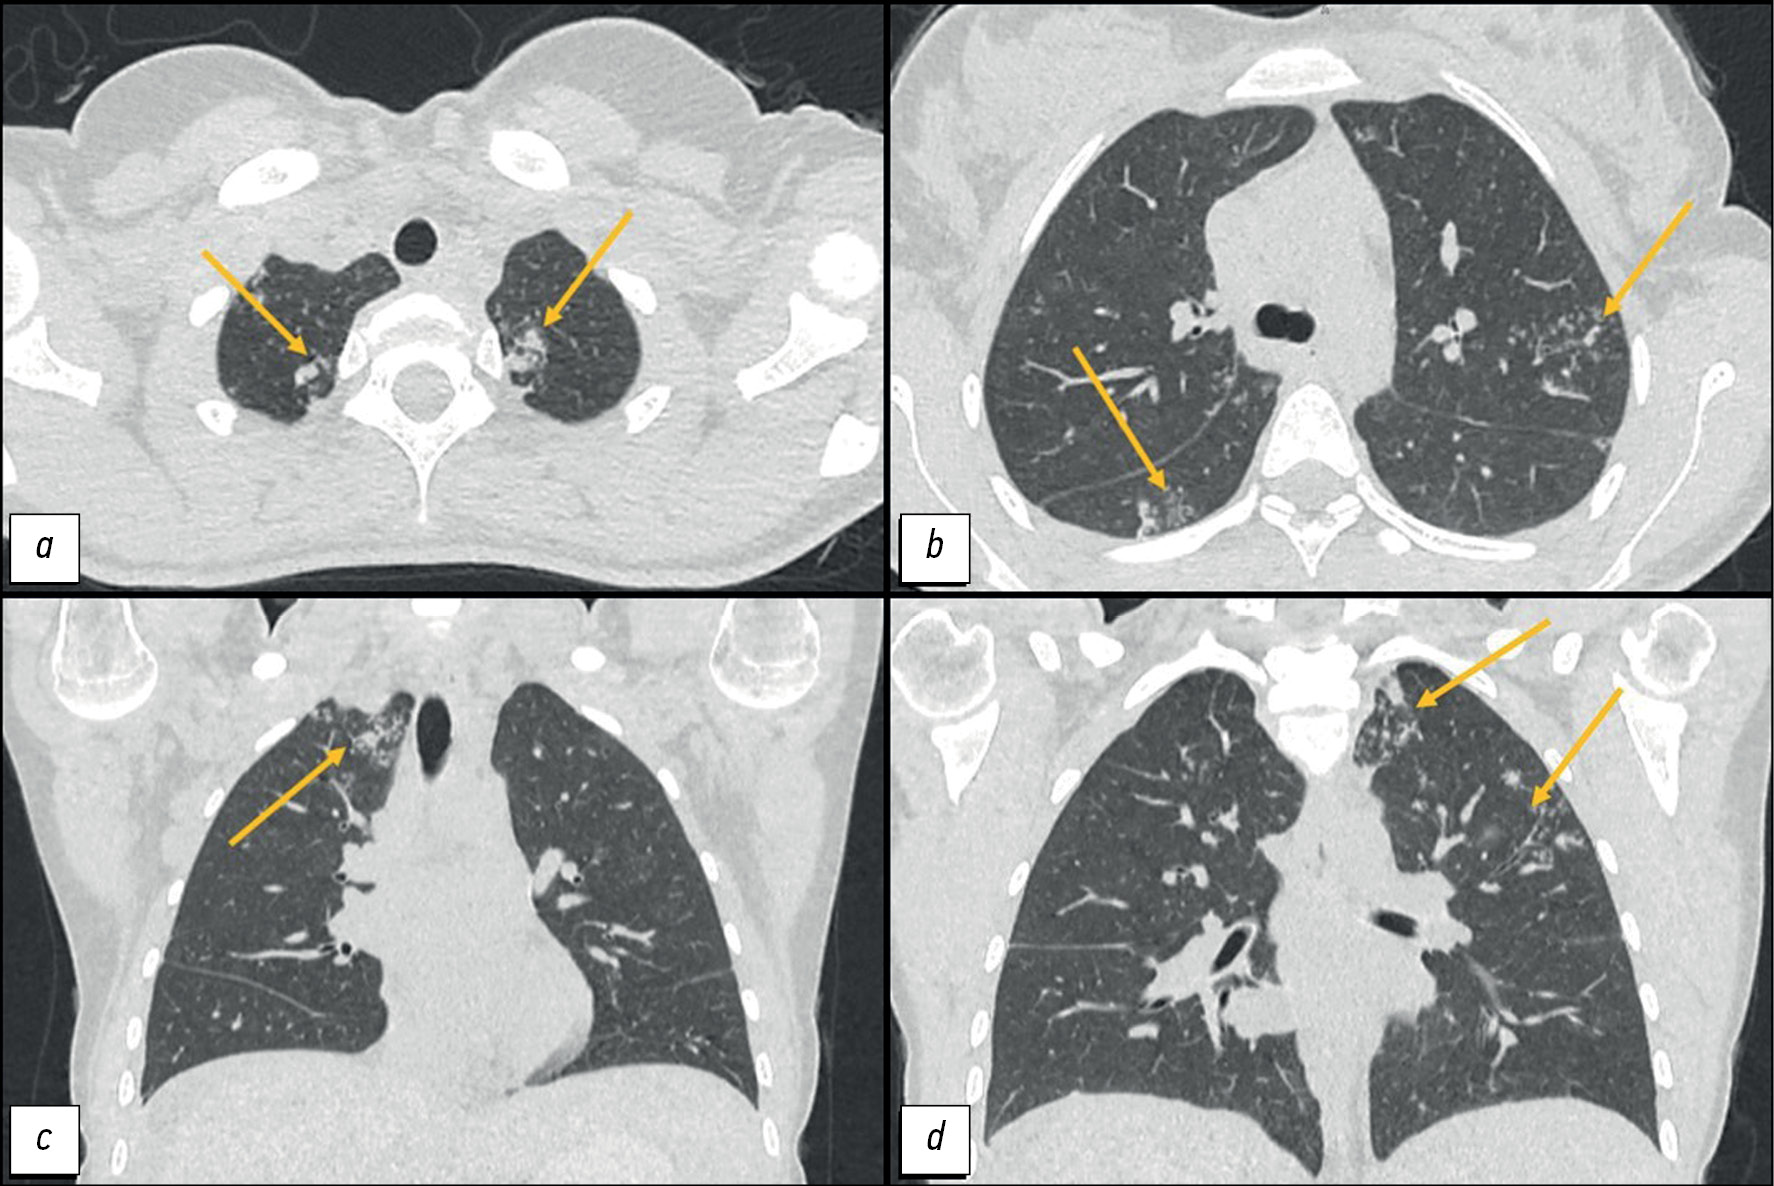

Difficulty in the differential diagnosis of peritoneal carcinomatosis and tuberculosis in a young female patient with ascites: a case report

Abstract

The differential diagnosis between peritoneal tuberculosis and peritoneal carcinomatosis is quite challenging because of the similarity of the clinical picture and laboratory and instrumental examination data. Peritoneal tuberculosis and peritoneal carcinomatosis may present with the development of ascites, lymph nodes, and intestinal loop conglomerates. This article presents the clinical case of a young patient who, after her second childbirth, noted the appearance of intense pain in the neck and between the scapulae. Two months later, she experienced pneumonia with a positive reaction to antibiotic therapy. After another 2 months, she experienced recurrent ascites and gastrointestinal symptoms for the first time. The examination revealed ovarian masses and signs of peritoneal carcinomatosis and lung nodules. However, the clinical presentation was atypical for peritoneal carcinomatosis, and lung lesions were suspicious for tuberculosis, which allowed us to hypothesize the presence of tuberculosis of multiple localizations. The diagnosis was confirmed by laparoscopy with a biopsy of the involved tissues and subsequent histological and laboratory confirmation of the etiological role of Mycobacterium tuberculosis. The described case demonstrates the importance of using all available diagnostic methods to establish the causes of ascites in young female patients for differential diagnosis between specific and neoplastic etiologies.

643-652